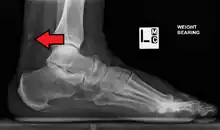

Calcification from dermatomyositis

X-Ray of the knee in a person with dermatomyositis.

Magnetic resonance imaging may be useful to guide muscle biopsy and to investigate involvement of internal organs;[11] X-ray may be used to investigate joint involvement and calcifications.[12]